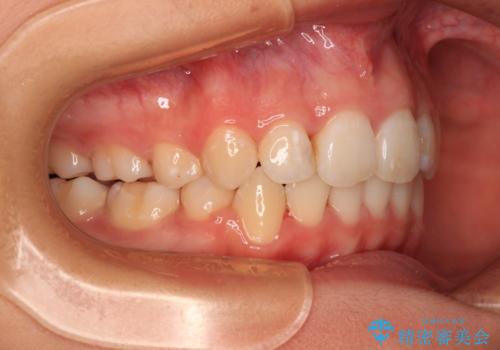

補助装置を併用したおかげでスムーズに奥歯の咬み合わせを改善することができ、我々も予想できないくらい理想的な仕上がりにすることができました。

補助装置を用いて奥歯の咬み合わせを改善しながら歯列を後方に移動させ、上下左右第一小臼歯を4本抜歯することで八重歯や口元の突出感を改善することとしました。